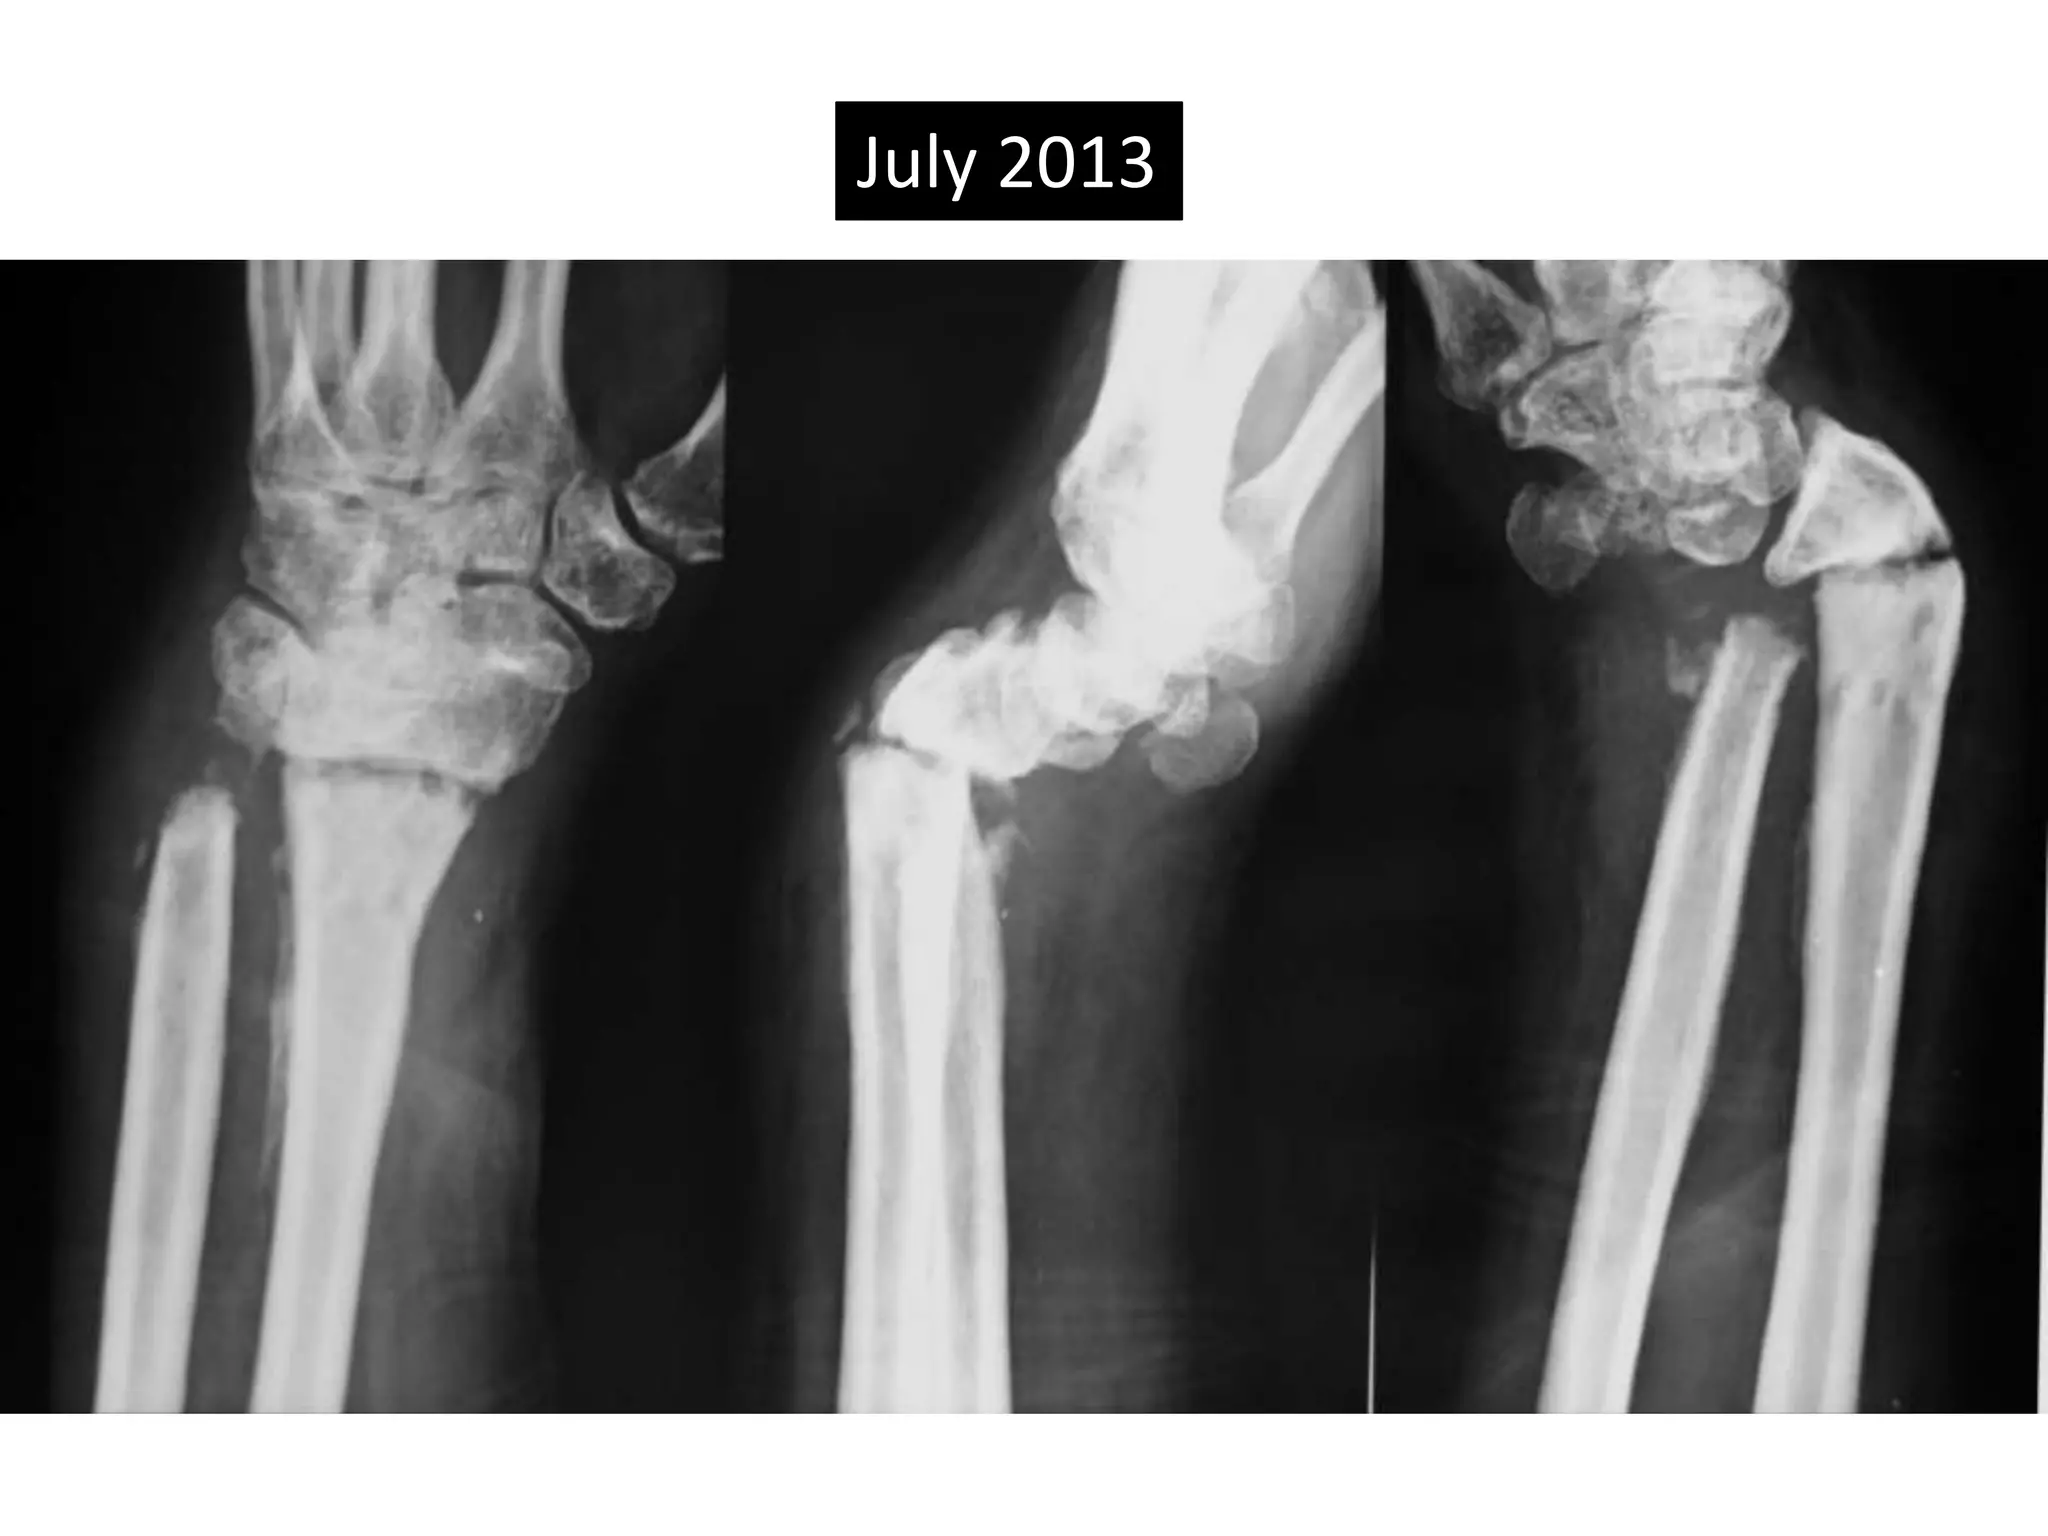

July 2013

Severe Palmer flexion and ulnar deviation deformity